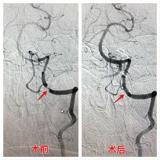

7月22日周六下午是医院正常休息时间,我院DSA导管室医护人员却忙碌着进行手术前的各项准备工作,因为今天北京宣武医院高鹏博士及我院神经介入团队经过周密计划决定为一例双侧椎动脉V4段重度狭窄的病人进行两枚支架植入手术。这是继上次我院首例锁骨下动脉狭窄、颈内动脉狭窄行支架植入手术后第一例颅内段血管狭窄支架植...2017-07-26